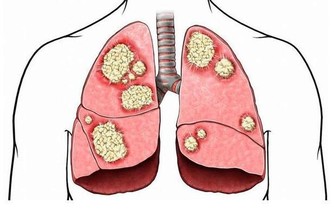

頻繁的社交讓男人極易感染各種肝炎病毒,酒桌上推杯換盞更是帶來不可逆轉的肝損傷。

再加上前列腺問題,給男人健康帶來巨大的隱患。但在關心自身健康方面,男人往往表現的比較遲鈍。

中國80%的重病男性在調查中承認,因為長期忽視健康小問題,所以讓身體再三透支。